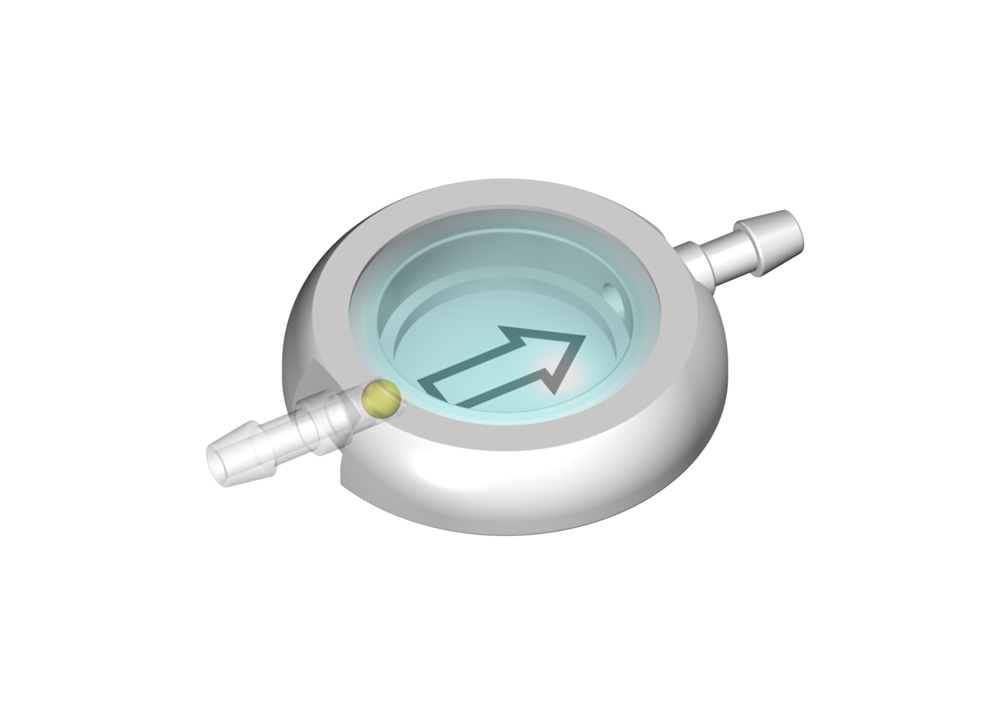

Ein solches CONTROL RESERVOIR bzw. eine Vorkammer ermöglicht die Messung des intraventrikulären Drucks, die Injizierung von Medikamenten und ggf. eine Ventilkontrolle. Eine Entnahme von Liqour und Zugabe von Medikamenten kann durch die Punktion der Silikonmembran mit einer Kanüle erfolgen. Der solide Titanboden verhindert dabei das Durchstechen mit einer Kanüle.

Die Reservoire sind für Katheter mit einem Innendurchmesser von ca. 1,2 mm und einem Außendurchmesser von ca. 2,5 mm ausgelegt (außer LP-Vorkammer).